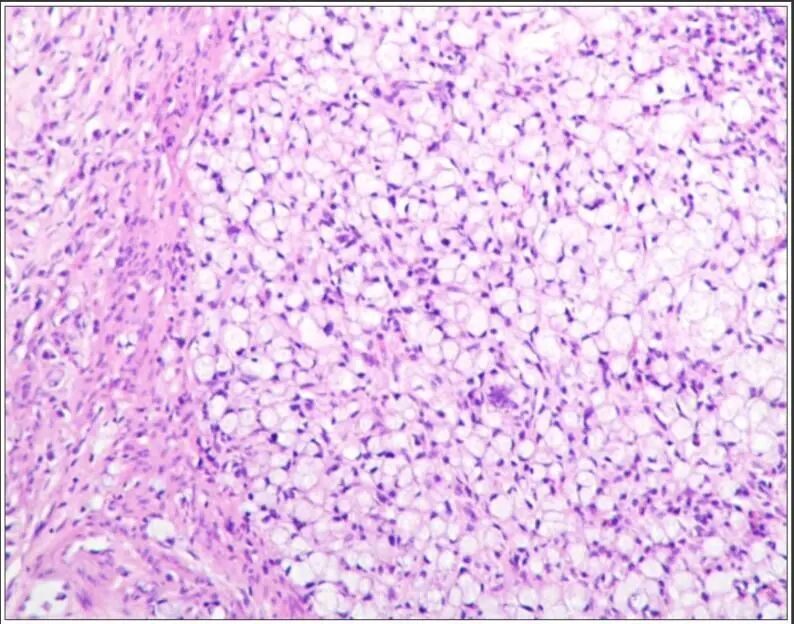

患者,女,63 岁,因右乳肿块一周入院,超声于右侧乳腺 10 点钟方向见一低回声结节,不规则形,边缘模糊(图 1),内部回声不均, CDFI 见较丰富血流信号(图 2), PW 测及高阻动脉血流频谱, RI:0.78 (图 3)。

术后病理提示浸润性导管癌(图 4)。

图 4 术后病理提示浸润性导管癌